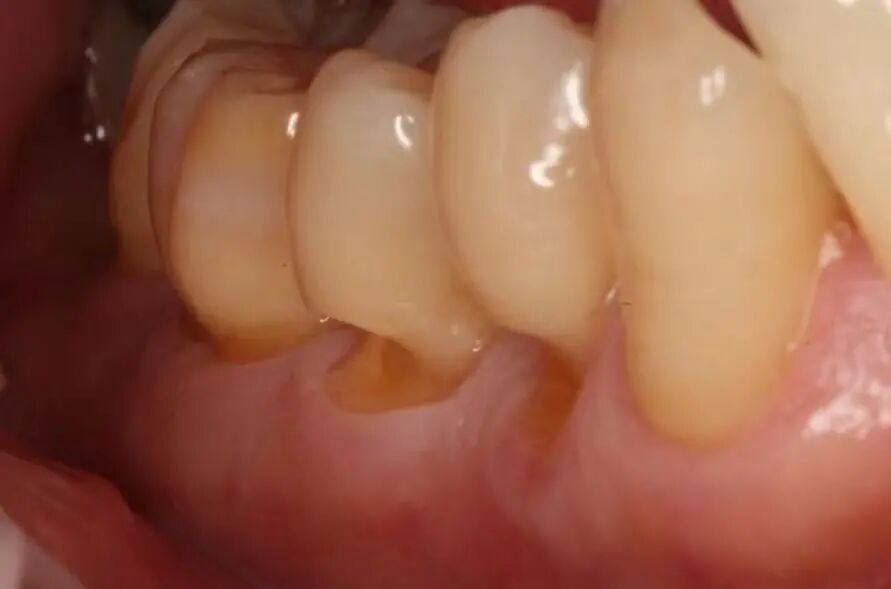

四. 如何判断自己有没有牙周病?